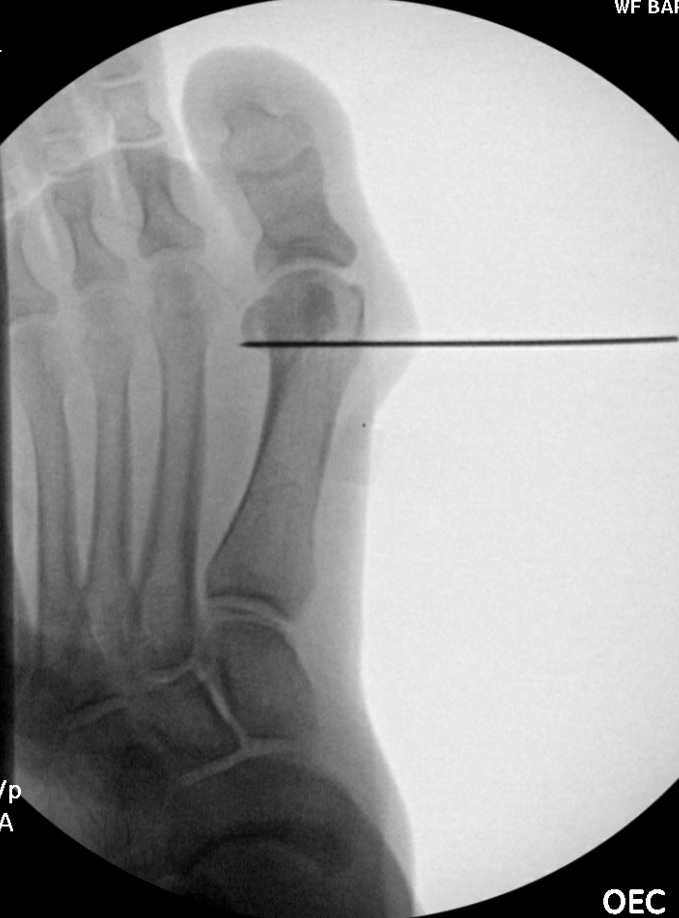

Anesthesia is often a combination of IV sedation and a local Mayo block. The surgeon applies an ankle tourniquet on a well-padded extremity before making a longitudinal skin incision overlying the first MTPJ just medial to the extensor tendon. The surgeon carries the incision down through the subcutaneous tissues, protecting neurovascular structures in the standard fashion. Next, one deepens the incision longitudinally through the capsule down to bone, and exposes the first metatarsophalangeal joint before freeing the medial and lateral capsular attachments. The surgeon resects the medial eminence of the first metatarsal head, carefully preserving the sagittal groove. Then, one drives a K-wire from medial-to-

lateral in the center of the metatarsal head perpendicular to the long axis of the first metatarsal (see second photo). Then, osteotomy creation takes place in the metatarsal head in a distal chevron style with the dorsal arm perpendicular to the weight-bearing surface, and the plantar arm approximately parallel with the weight-bearing surface. Translation of the metatarsal head is approximately 3 to 6 mm laterally at the surgeon's discretion. After obtaining the appropriate translation, one applies manual compression through the osteotomy site.